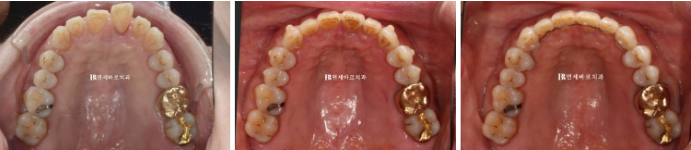

어금니 교합이 원래 좋은 편이셨기에 전략적으로 원래 교합을 유지하며 치료를 진행했습니다.

어린 친구들과 다르게 수십년간 같은 교합으로 지내오신 관성이 있어서 어금니 교합이 바뀌면 많이 불편해하십니다.

중년 교정이기에 젊은 분들과 조금 다르게 접근해야 하는 부분입니다.

23.1~23.7

인비절라인 치료 중에는 치아에 어태치먼트가 필요합니다.

인비절라인으로 교정이 잘 안 되던 과거와 현재가 명확히 나뉘는 기준이 바로 이 어태치먼트의 유무입니다.

23.01~23.07